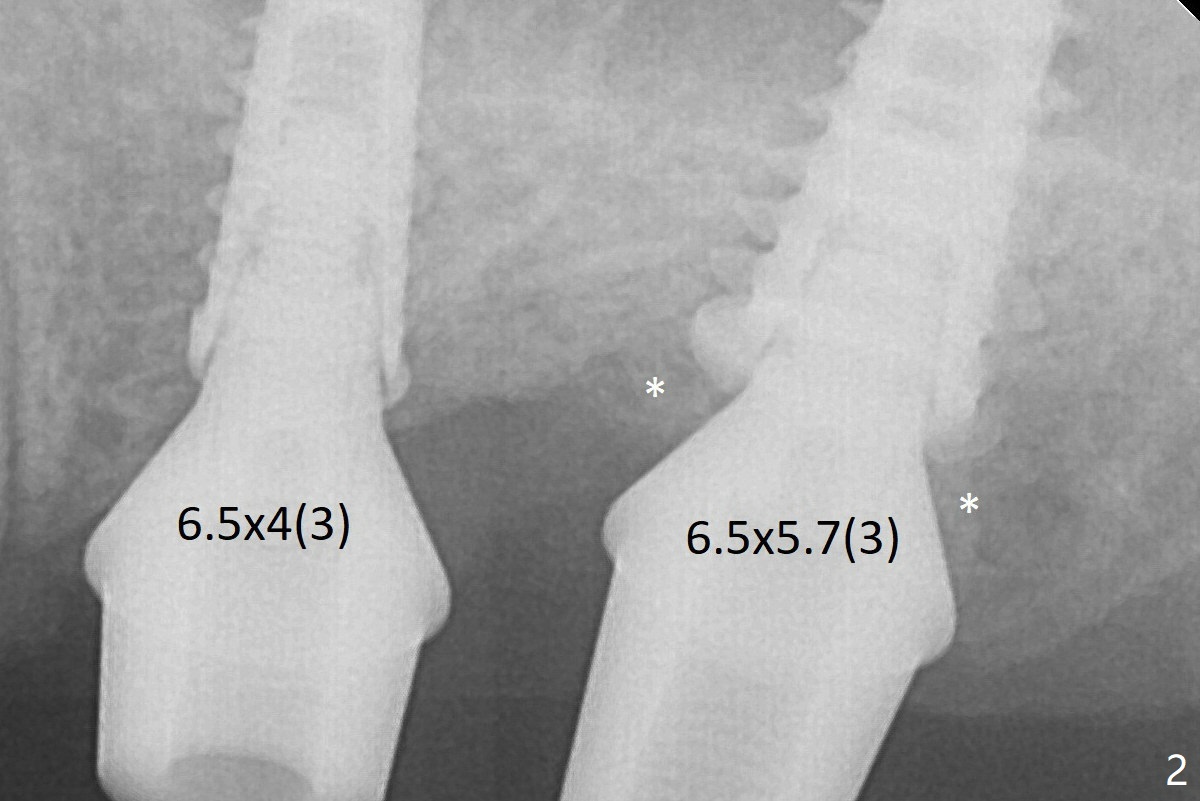

After adjustment of trajectory, a 4x11 mm definitive implant is placed at #14 with ~ 35 Ncm, while a 6x9 mm implant is placed at #15 with ~35 Ncm (Fig.2 (*: Vanilla Graft with Osteogen)).  The patient returns 3 months postop (Fig.3).  After changing abutments to 5.5x5.7(3) mm, impression is taken.  While there is distal bone resorption (arrow (due to the large abutment/pressure?)), the mesial bone graft retains (*).